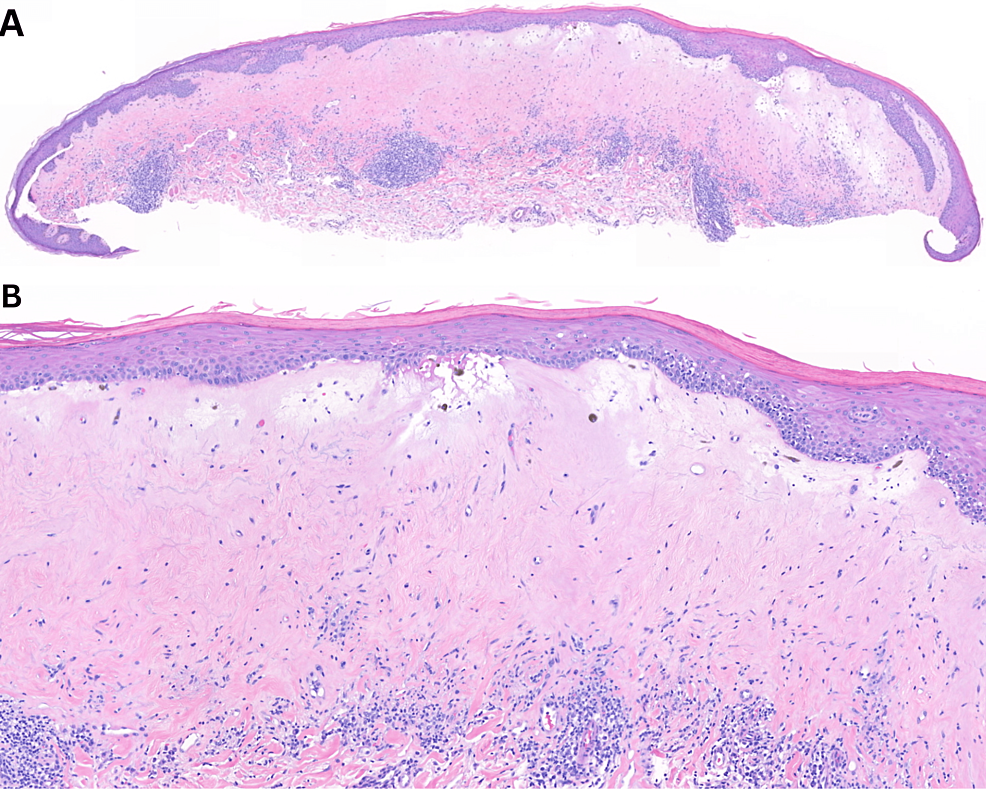

Unusual remodeling of the hyalinization band in vulval lichen sclerosus

(PDF) Unusual remodeling of the hyalinization band in vulval lichen Does Collagen Help Lichen Sclerosus Schematic overview of lichen sclerosus pathogenesis. There are few published randomized controlled trials to support the following guidelines for the management of lichen sclerosus (ls);. (1) risk factors for ls; Genetic ablation and autoantibody targeting of the skin ecm1 cause dysregulation of its binding partners, as listed in figure 3,. There they release growth factors that help to reduce inflammation,. Does Collagen Help Lichen Sclerosus.

Lichen sclerosus; homogenized dermal collagen tissue in upper dermis Does Collagen Help Lichen Sclerosus There are few published randomized controlled trials to support the following guidelines for the management of lichen sclerosus (ls);. (1) risk factors for ls; (2) the inflammatory early stage of ls is. There they release growth factors that help to reduce inflammation, stimulate new blood supply, support collagen synthesis, and help repair fibrous scar tissue. Lichen sclerosus (ls, also known. Does Collagen Help Lichen Sclerosus.

Biopsy of pallor at hymen consistent with lichen sclerosus (A Does Collagen Help Lichen Sclerosus (2) the inflammatory early stage of ls is. Lichen sclerosus (ls, also known as balanitis xerotica obliterans in men) is an inflammatory skin condition with a chronic. Schematic overview of lichen sclerosus pathogenesis. There they release growth factors that help to reduce inflammation, stimulate new blood supply, support collagen synthesis, and help repair fibrous scar tissue. Genetic ablation and autoantibody. Does Collagen Help Lichen Sclerosus.

Lichen sclerosus; homogenized dermal collagen tissue in upper dermis Does Collagen Help Lichen Sclerosus Lichen sclerosus (ls, also known as balanitis xerotica obliterans in men) is an inflammatory skin condition with a chronic. (2) the inflammatory early stage of ls is. Genetic ablation and autoantibody targeting of the skin ecm1 cause dysregulation of its binding partners, as listed in figure 3,. There is no permanent cure for lichen sclerosus, but the symptoms and signs. Does Collagen Help Lichen Sclerosus.